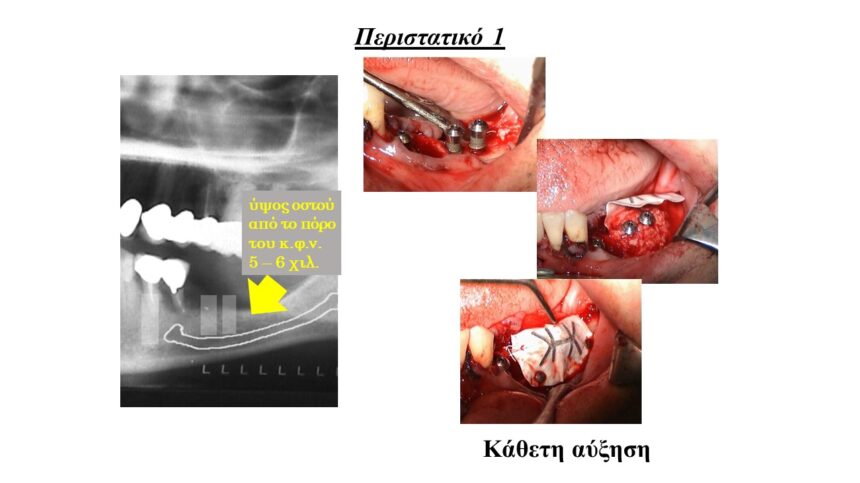

Τρισδιάστατη οστική ανάπλαση της ακρολοφίας με χρήση απορροφήσιμων , μη απορροφήσιμων μεμβρανών και μοσχευμάτων. Ενδείξεις, αντεδείξεις, πλεονεκτήματα - μειονεκτήματα.